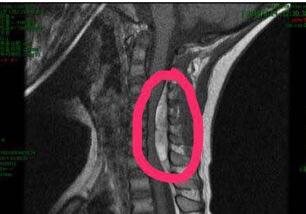

CT片显示,琦琦椎管内有出血,压迫了神经,导致他出现瘫痪症状。武汉儿童医院神经外科主任杜浩主刀为他做了手术,清除血块,之后给与对症治疗。一家人后怕不已,好在琦琦的病情逐渐好转。 26日,琦琦基本恢复正常,康复出院。